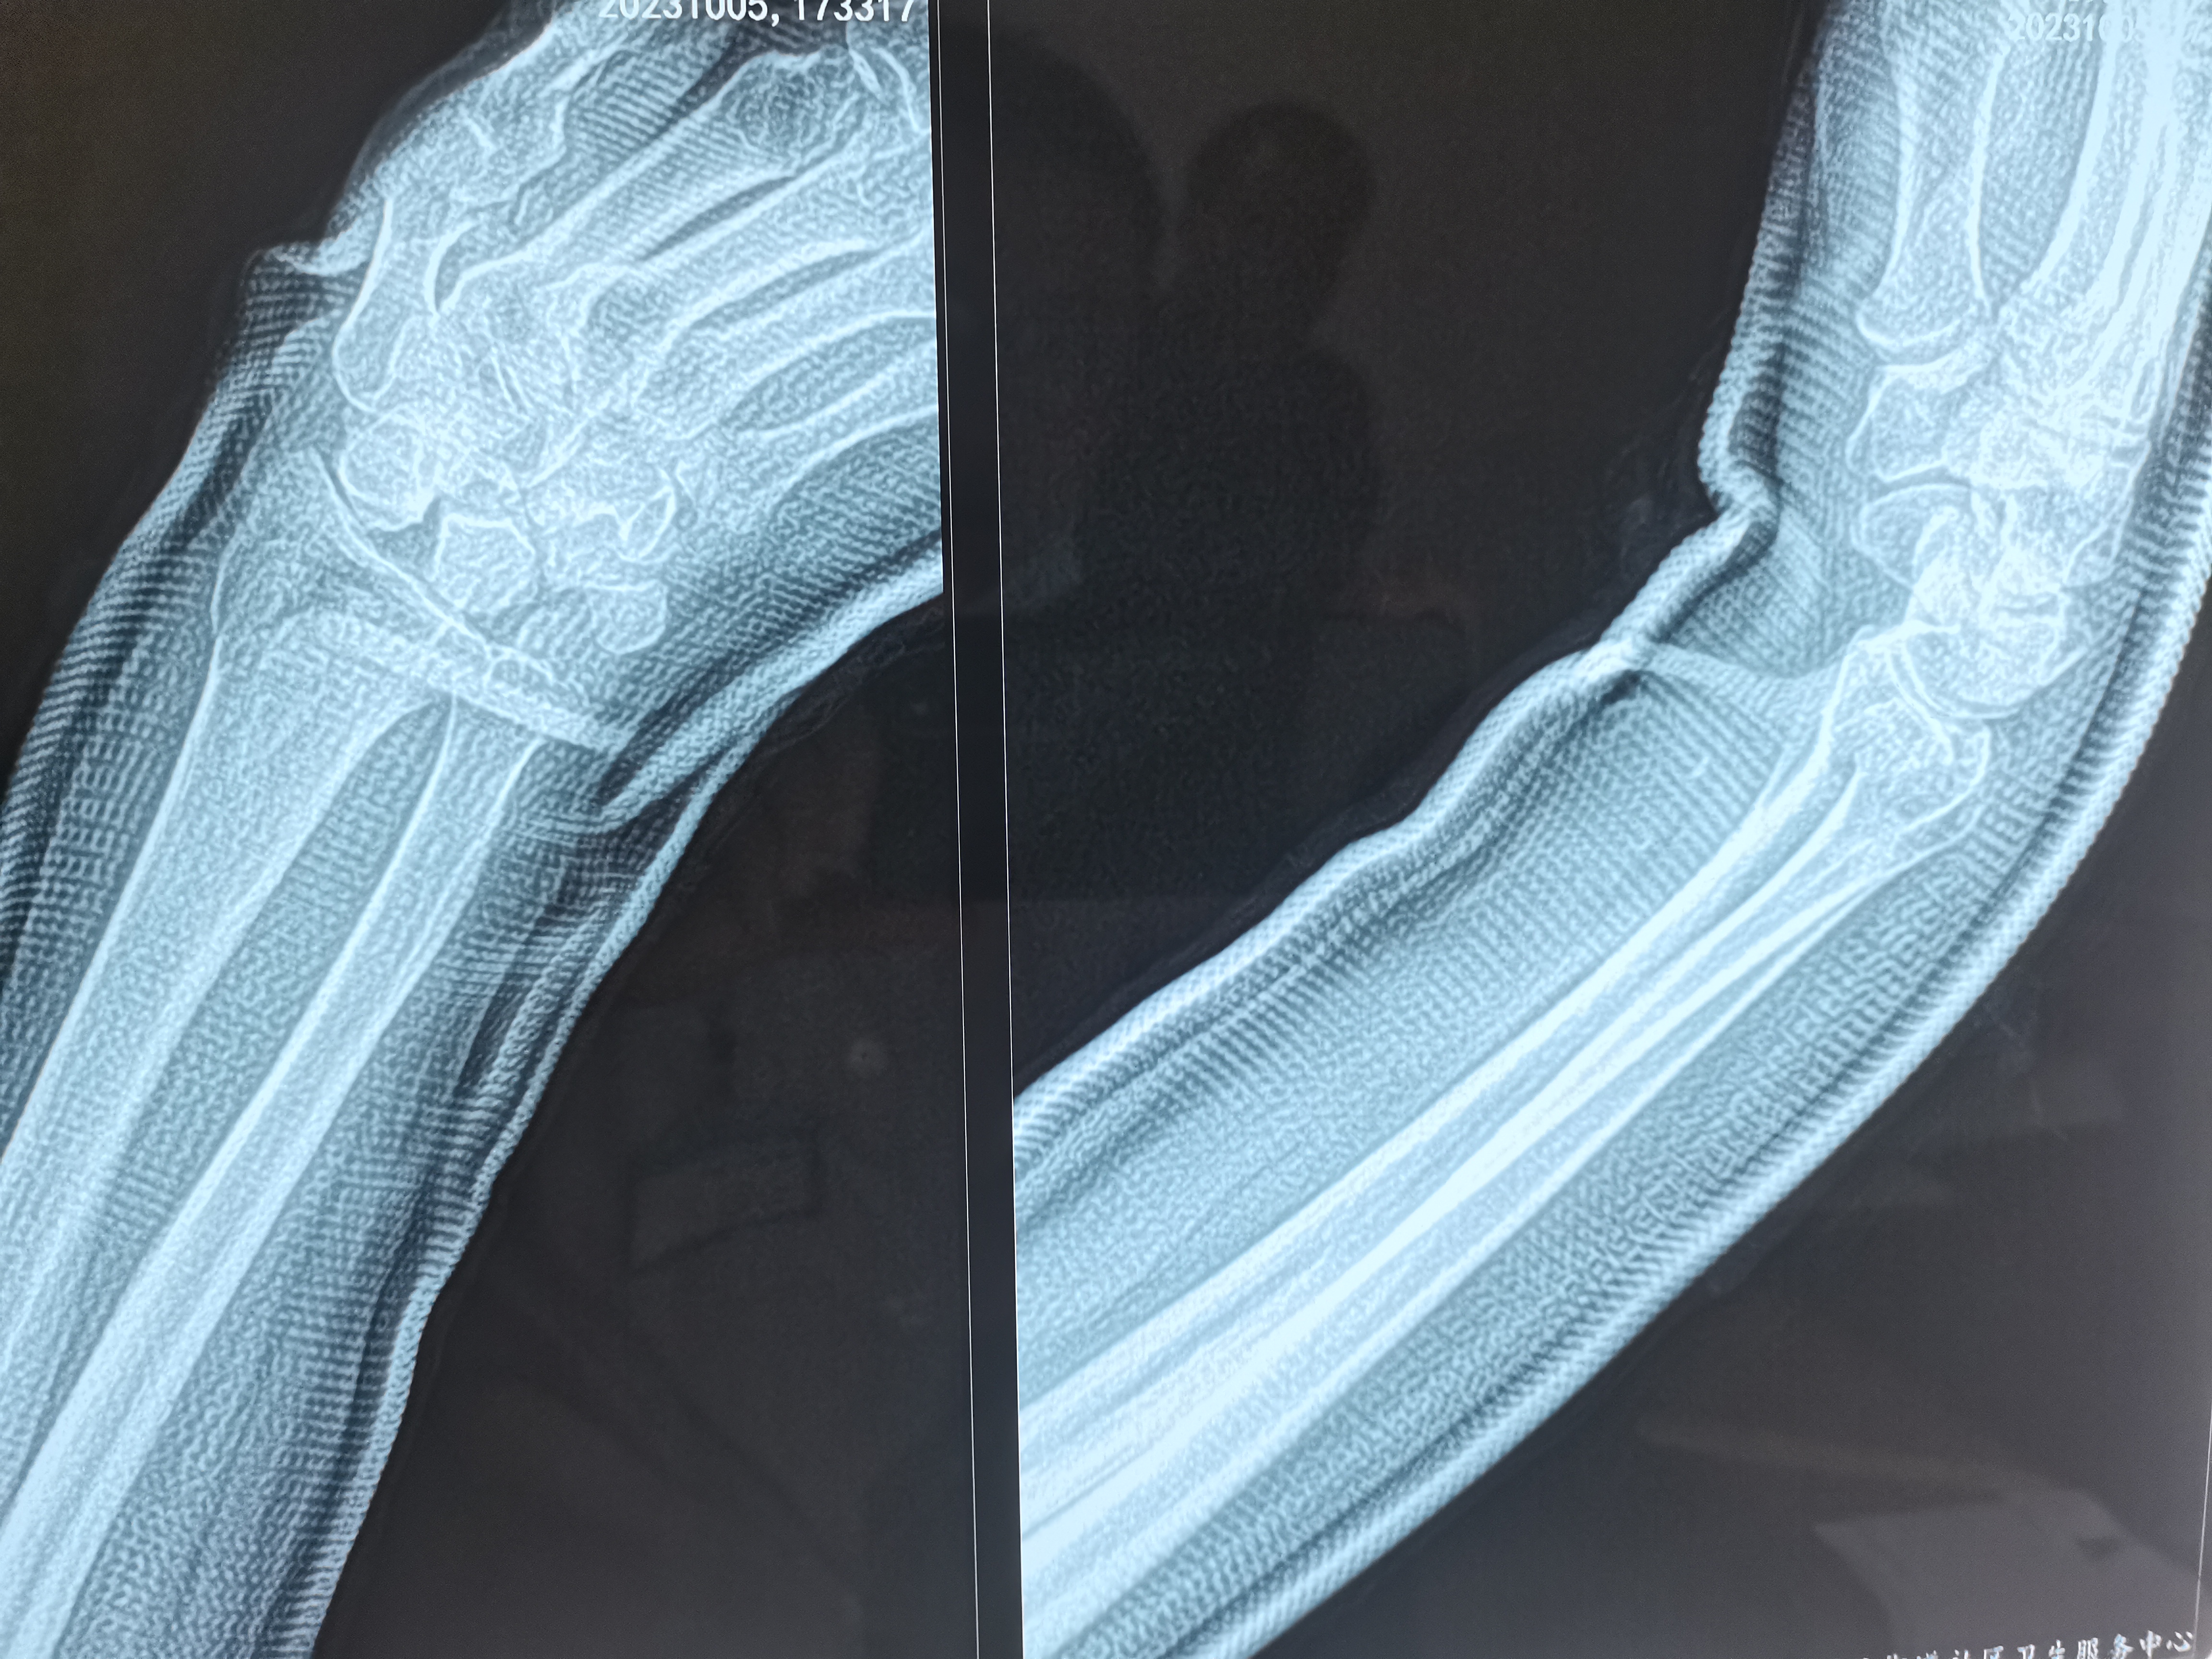

1. 评估病情:通过X线片明确骨折类型(如Colles骨折、Smith骨折、Barton骨折)、移位方向(掌侧/背侧移位、桡侧偏移、短缩等),同时检查腕部神经(正中神经为主)、血管功能。

以常见的Colles骨折(背侧移位)为例,复位步骤如下:

3. 调整掌倾角与尺偏角:通过微调牵引力方向,使桡骨远端掌倾角恢复至10°-15°,尺偏角恢复至20°-25°,此时可触及骨折端稳定的骨擦音。

1. 影像学检查:复位后即刻复查X线片,确认骨折对位对线良好,若仍有移位需再次复位。

手法复位的成功与否取决于对骨折移位规律的掌握和操作技巧的熟练度,复位后定期复查X线片(复位后即刻、1周、2周、4周)至关重要。多数患者通过规范的手法复位和后续康复,可恢复良好的腕关节功能。